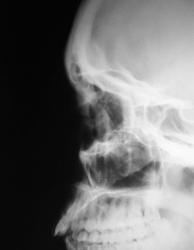

Женьщина 1983 года рождения, получила удар кулаком в лицо, каторый прошел справа налево, по касательной переносицу, левое глазное яблоко и левую бровь. Внешне слева выраженная параорбитальная гематома. Выполнены рентгенограммы глазниц с интервалом в 2 дня.

Клинически данных за перелом левой глазницы нет. Мне не нравится то что контуры левого глазного яблока такие четкие. Могла ли интраорбитальная эмфизема быть причиной такой четкости контуров глазного яблока? Есть ли она на представленных рентгенограммах? Я подозреваю разрывной перелом стенки левой глазницы, понимаю что КТ может решить этот вопрос, но КТ у нас нет.

Создаётся впечатление о переломе верхнего края левой глазницы глазницы.

Я считаю, что есть.Более выраженная на первом снимке.

Мне кажется это нормальная картина канала n. supraorbitalis.

А эмфизема слева очень вероятна

На мой взгляд, эмфизема мягких тканей - вообще не предмет для рентгензаключения. Если пальпаторно есть крепитация, значит есть эмфизема мягких тканей. Наше дело переломы. Если они видны. Напрмер, перелом (даже вдавленный) медиальной стенки глазницы (решетчатых клеток) практически невозможно увидеть на рутинной рентгенограмме. А воздух, в данном случае, и под веком может быть.

Мне кажется, есть. На 1 снимке более выраженная. Воздух, конечно, может быть и под веком, но веко так к носу не уходит.

Эмфизема есть. Вероятнее всего перелом медиальной стенки орбиты. Можно попробовать томограммы, хотя оптимальна КТ.

Сасибо за мнения коллеги, в заключении прозвучала эмфизема как косвенный признак перелома стенки орбиты смежной с параназальной пазухой.